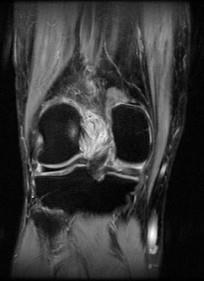

问题 男,50岁,膝关节侧方疼痛,请结合影像图像,选择最可能的诊断 ( )

选项 A、前十字韧带囊肿 B、膝关节腔积液 C、滑膜型关节结核 D、前十字韧带黏液样变性 E、化脓性关节炎

答案 D